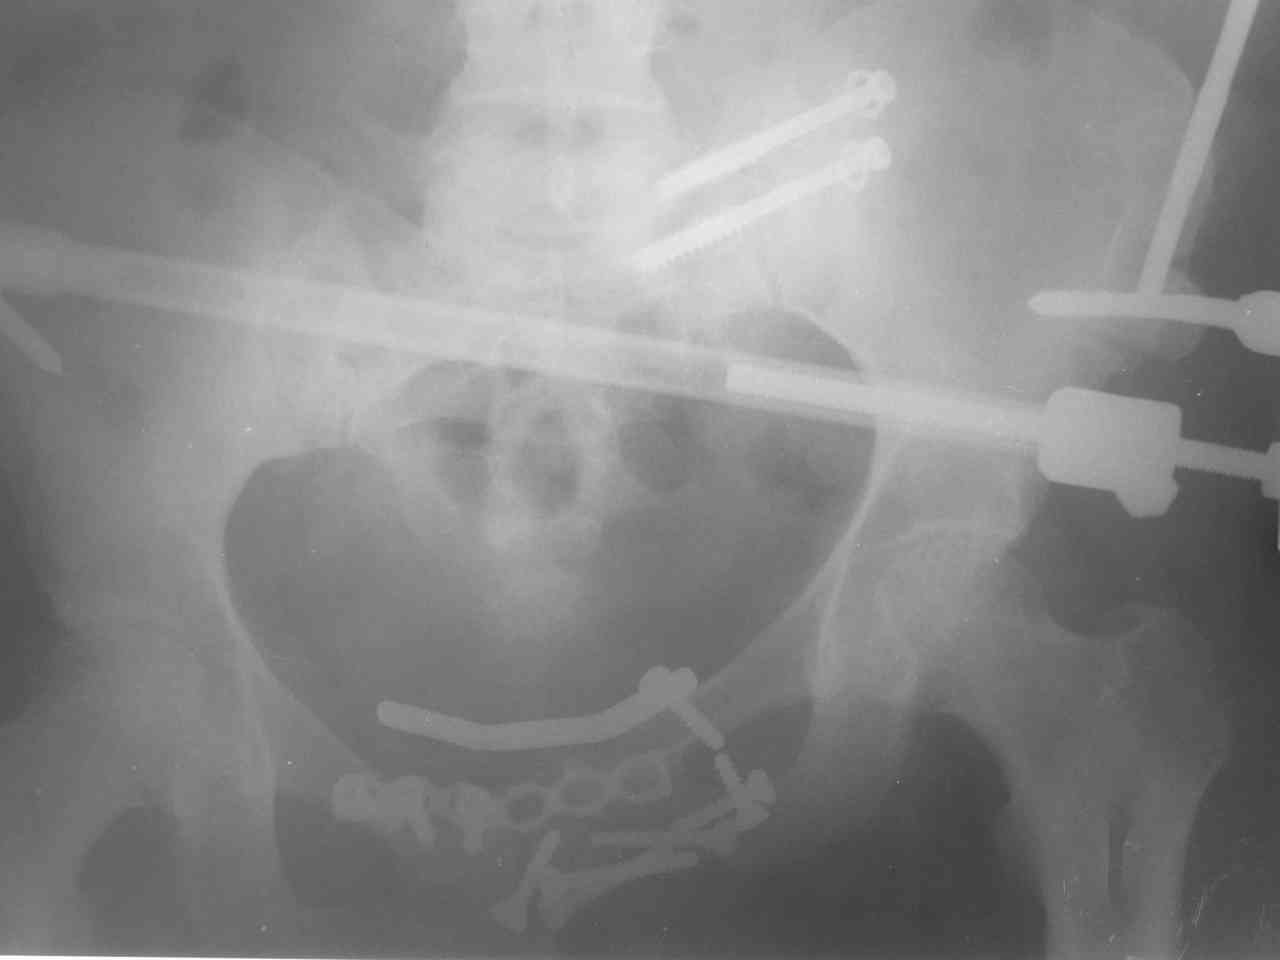

Пациентка получила травму таза 9 месяцев назад (перелом латеральной массы крестца слева, разрыв лонного сочленения).

Лечилась в стационаре другого города, без успеха. В мае 2007 прооперирована в нашем отделении, выполнена открытая репозиция повреждений, остеосинтез винтами латеральной массы крестца и пластинами лонного сочленения. Дополнительная фиксация аппаратом внешней фиксации. 3 недели спустя упала в палате на ягодицы, при этом получила повторную травму таза, смещение отломков. Уважаемые коллеги каково ваше мнение о способе фиксации полученных повреждений. С уважением Алексей.